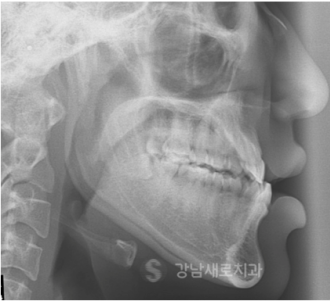

교정 전/후

하지만 이러한 양악전 교정은

수술 전 6개월~1년 정도의

교정 치료 기간이 필요하며,

수술 후 마무리 교정에도 6개월~1년 정도의

기간이 소요되기 때문에 교정 기간이

상대적으로 길다는 단점이 있었어요.